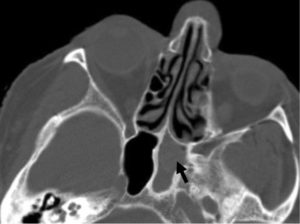

Для диагностики сфеноидита необходимо выполнение Компьютерной томографии (КТ) пазух носа.

Рентгенография черепа – еще один метод диагностики, который позволяет уточнить, есть или нет сфеноидит. Особенно высока ее диагностическая ценность при экссудативной форме воспаления, когда обнаруживается уровень жидкости в пазухе.

Нередко, особенно при хроническом течении, врачи прибегают к проведению компьютерной томографии. С ее помощью удается послойно оценить строение носа и придаточных его пазух. Главное преимущество этого метода – это возможность определить размер соустий, который влияет на частоту рецидивов заболевания и отражается на тактике лечения.

К дополнительным методам относится, например, носовая эндоскопия. Тем не менее, одной только эндоскопии носа также недостаточно, т.к. примерно в 50-60% случаев эндоскопия не выявляет ничего патологического. Обычная рентгенография черепа мало информативна и, как правило, бесполезна.

Единственными методами, которые наверняка могут определить сфеноидит, являются компьютерная томография (КТ) или магнитно-резонансная томография (МРТ) –